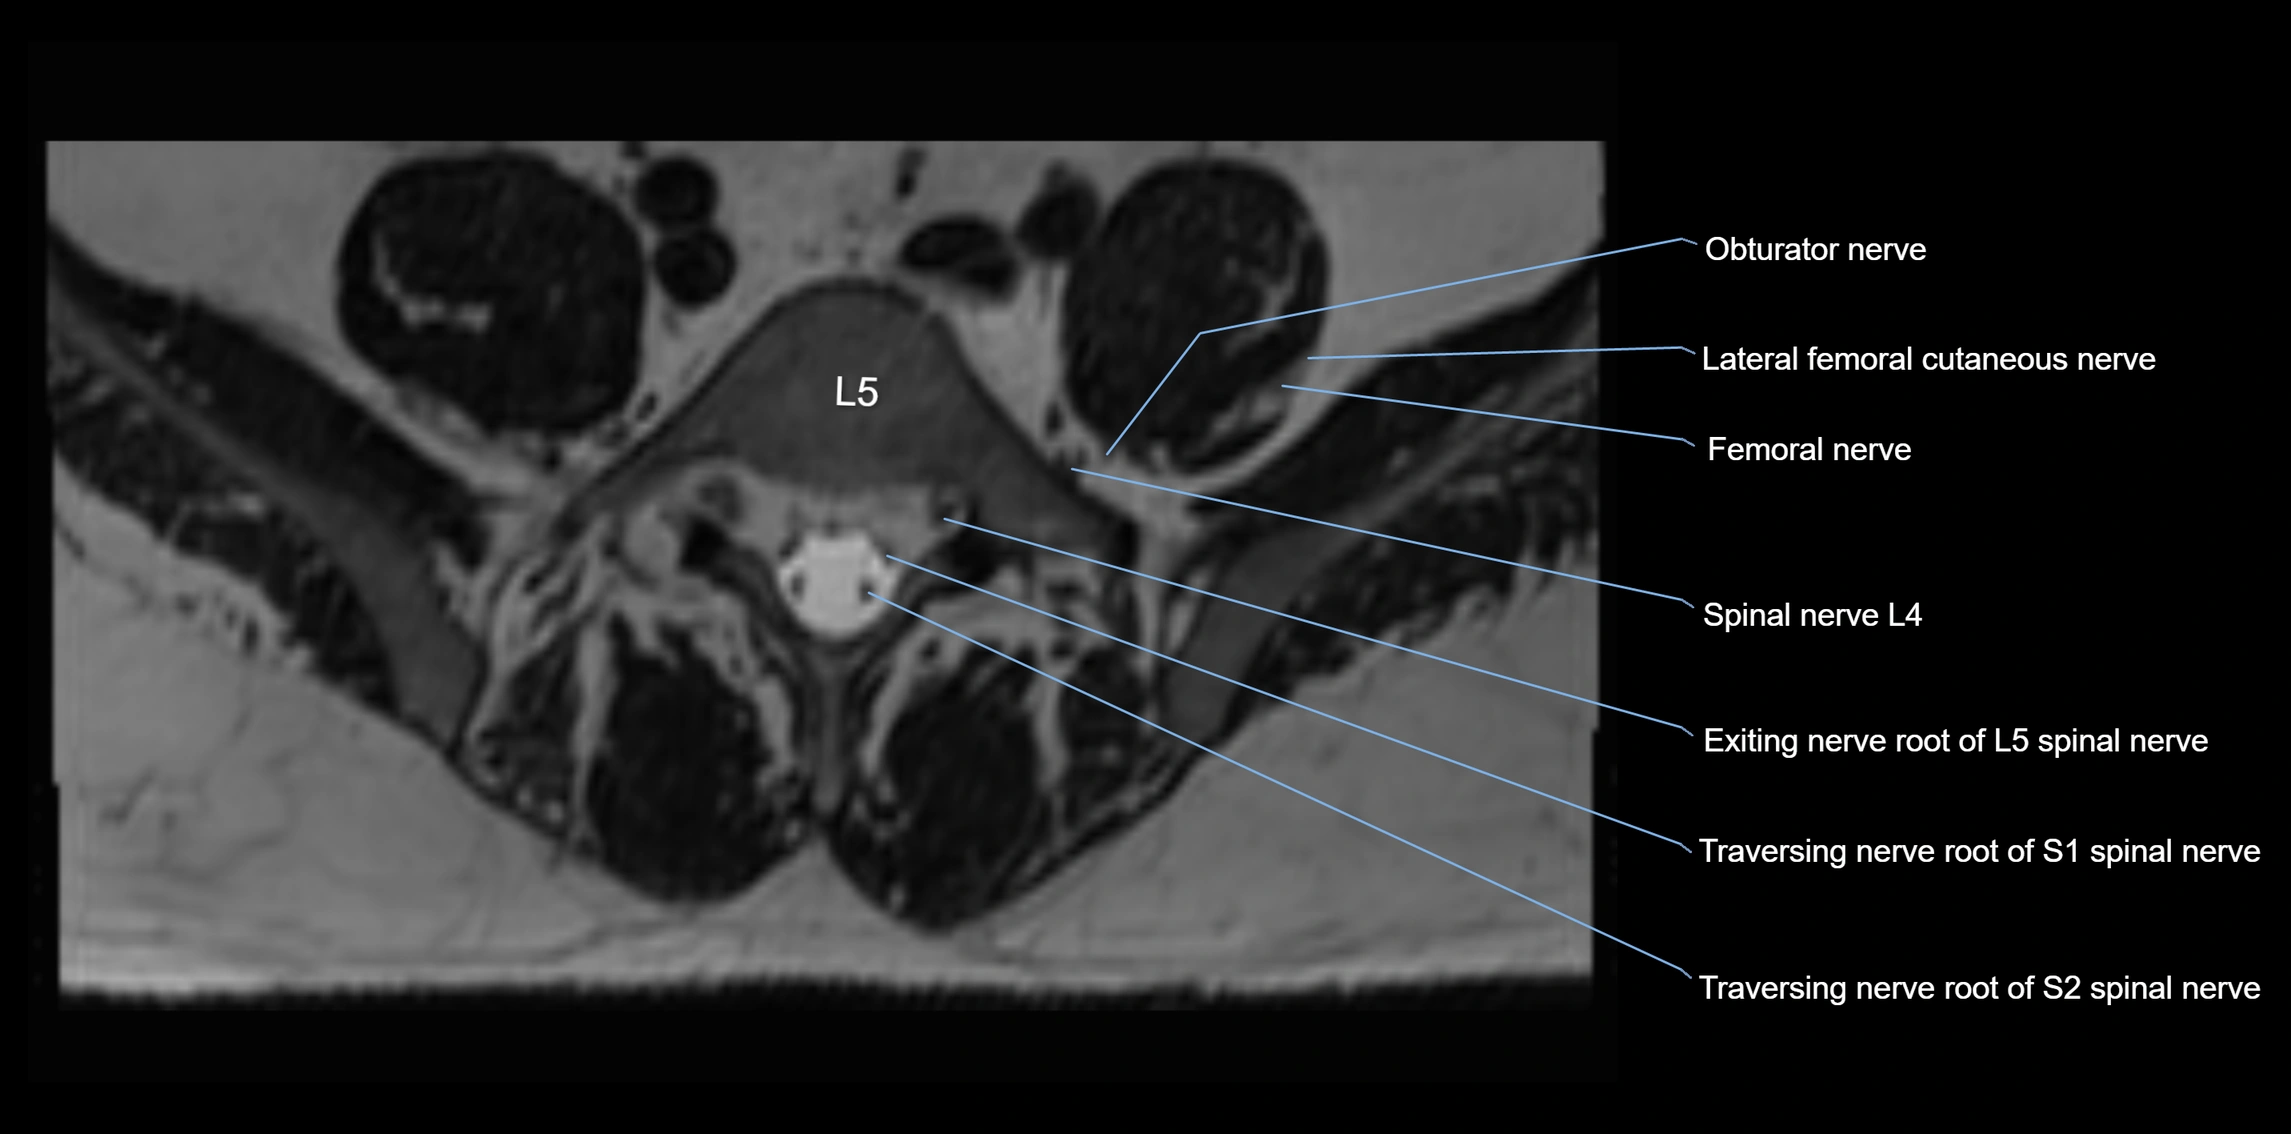

MRI Appearance

T1-weighted images:

• Nerve appears as a very thin low-to-intermediate signal intensity structure

• Surrounded by bright fat, aiding visualization

T2-weighted images:

• Nerve shows intermediate to mildly hyperintense signal compared to muscle

• Pathological involvement appears brighter

STIR (Short Tau Inversion Recovery):

• Normal nerve appears dark

• Inflamed or entrapped nerve appears bright hyperintense

T1 Fat-Sat Post-Contrast:

• Normal nerve enhances minimally

• Pathologic nerve (neuritis, entrapment, tumor infiltration) shows focal or diffuse enhancement

3D T2 SPACE / CISS:

• Nerve appears intermediate to mildly hyperintense compared to muscle

• Surrounded by bright fat or CSF, improving visualization

• Best sequence for mapping small pelvic nerves such as the anococcygeal